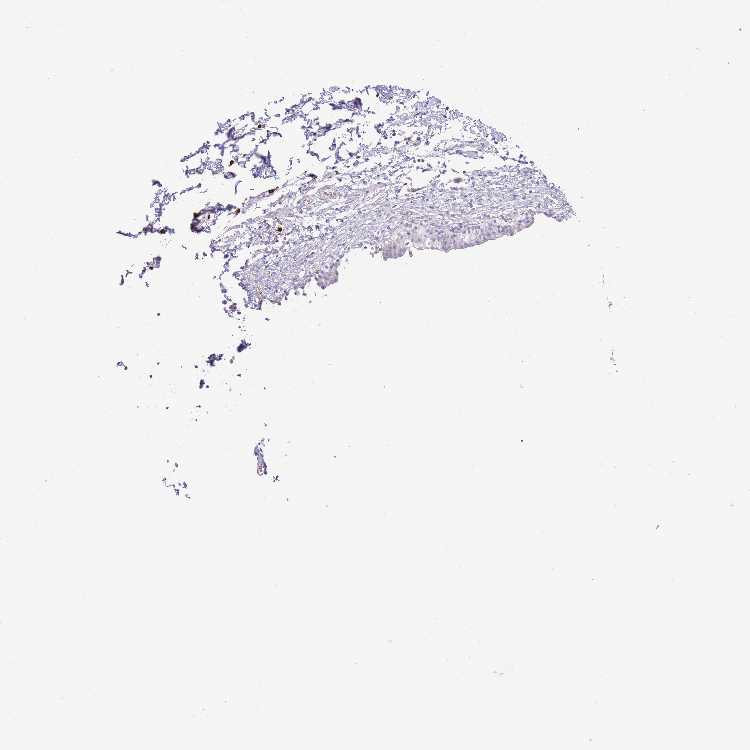

URINARY BLADDER - Antibody stainingi

Antibody staining in the annotated cell types in the current human tissue is reported as not detected, low, medium, or high, based on conventional immunohistochemistry profiling in selected tissues. This score is based on the combination of the staining intensity and fraction of stained cells.

Each image is clickable and will lead to virtual microscopy that enables deeper exploration of all samples and also displays staining intensity scores, fraction scores and subcellular localization as well as patient and tissue information for each sample.

Antibody HPA049153Antibody HPA049554

Urothelial cells Not detectedNot detected